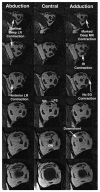

Methods: Five male and three female affected members of two autosomal dominant DURS2 pedigrees were enrolled in the study. Coronal T(1)-weighted MRI of the orbits was obtained in multiple gaze positions, as well as with heavy T(2) weighting in the plane of the cranial nerves. MRI findings were correlated with motility. V体育安卓版.

Results: All subjects had unilateral or bilateral limitation of abduction, or of both abduction and adduction, with palpebral fissure narrowing and globe retraction in adduction. Orbital motor nerves were typically small, with the abducens nerve (cranial nerve [CN]6) often nondetectable. Lateral rectus (LR) muscles were structurally abnormal in seven subjects, with structural and motility evidence of oculomotor nerve (CN3) innervation from vertical rectus EOMs leading to A or V patterns of strabismus in three cases V体育ios版. Four cases had superior oblique, two cases superior rectus, and one case levator EOM hypoplasia. Only the medial and inferior rectus and inferior oblique EOMs were spared. Two cases had small CN3s. .